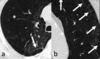

A

Patrón intersticial reticular